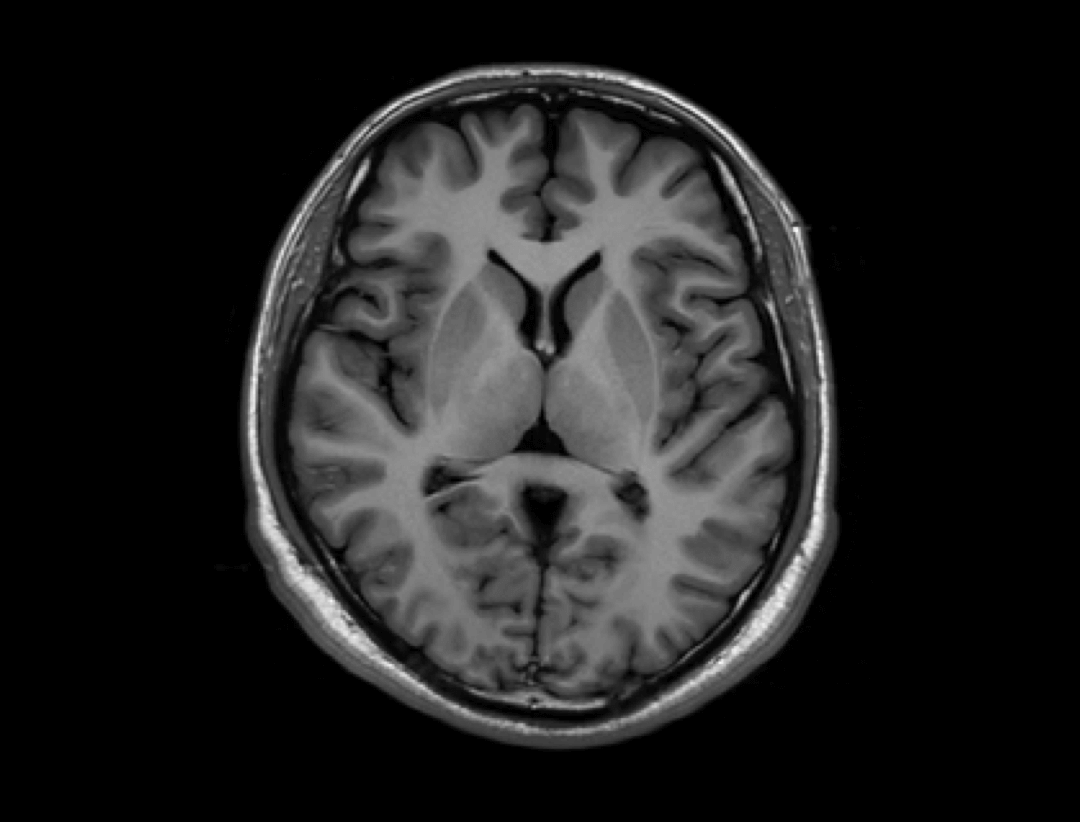

智云平台

智云磁体

自主研发的匀场技术,优异的磁场均匀度。

智云梯度

智能涡流补偿技术,高梯度性能。